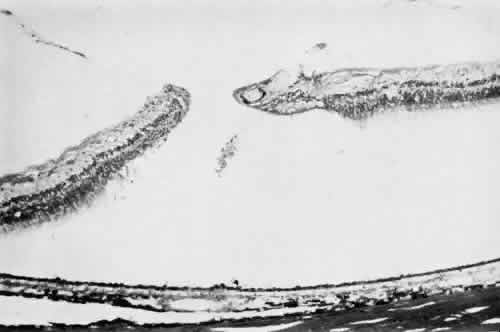

Fig. 10. Microsection of meridional complex through atypical dentate process and

its meridional fold. Anteriorly (on the left) the complex shows marked

redundancy of pigmented epithelium in its outer aspect and a dense glial

plaque on its inner aspect. Posteriorly (on the right) there is microcystoid

change, nonspecific degeneration, and dense-staining glial

cells along its surface. (Hematoxylin-eosin; × 63.) Fig. 10. Microsection of meridional complex through atypical dentate process and

its meridional fold. Anteriorly (on the left) the complex shows marked

redundancy of pigmented epithelium in its outer aspect and a dense glial

plaque on its inner aspect. Posteriorly (on the right) there is microcystoid

change, nonspecific degeneration, and dense-staining glial

cells along its surface. (Hematoxylin-eosin; × 63.)